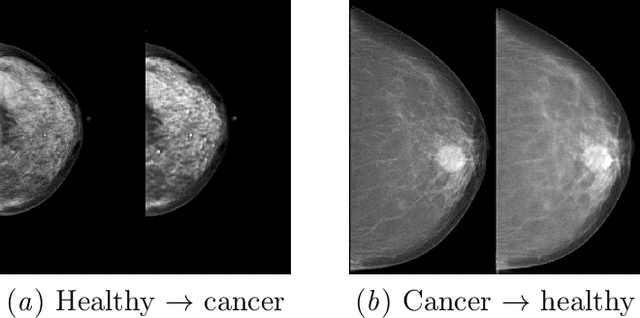

Abstract:$\textbf{Purpose}$ To train a cycle-consistent generative adversarial network (CycleGAN) on mammographic data to inject or remove features of malignancy, and to determine whether these AI-mediated attacks can be detected by radiologists. $\textbf{Material and Methods}$ From the two publicly available datasets, BCDR and INbreast, we selected images from cancer patients and healthy controls. An internal dataset served as test data, withheld during training. We ran two experiments training CycleGAN on low and higher resolution images ($256 \times 256$ px and $512 \times 408$ px). Three radiologists read the images and rated the likelihood of malignancy on a scale from 1-5 and the likelihood of the image being manipulated. The readout was evaluated by ROC analysis (Area under the ROC curve = AUC). $\textbf{Results}$ At the lower resolution, only one radiologist exhibited markedly lower detection of cancer (AUC=0.85 vs 0.63, p=0.06), while the other two were unaffected (0.67 vs. 0.69 and 0.75 vs. 0.77, p=0.55). Only one radiologist could discriminate between original and modified images slightly better than guessing/chance (0.66, p=0.008). At the higher resolution, all radiologists showed significantly lower detection rate of cancer in the modified images (0.77-0.84 vs. 0.59-0.69, p=0.008), however, they were now able to reliably detect modified images due to better visibility of artifacts (0.92, 0.92 and 0.97). $\textbf{Conclusion}$ A CycleGAN can implicitly learn malignant features and inject or remove them so that a substantial proportion of small mammographic images would consequently be misdiagnosed. At higher resolutions, however, the method is currently limited and has a clear trade-off between manipulation of images and introduction of artifacts.